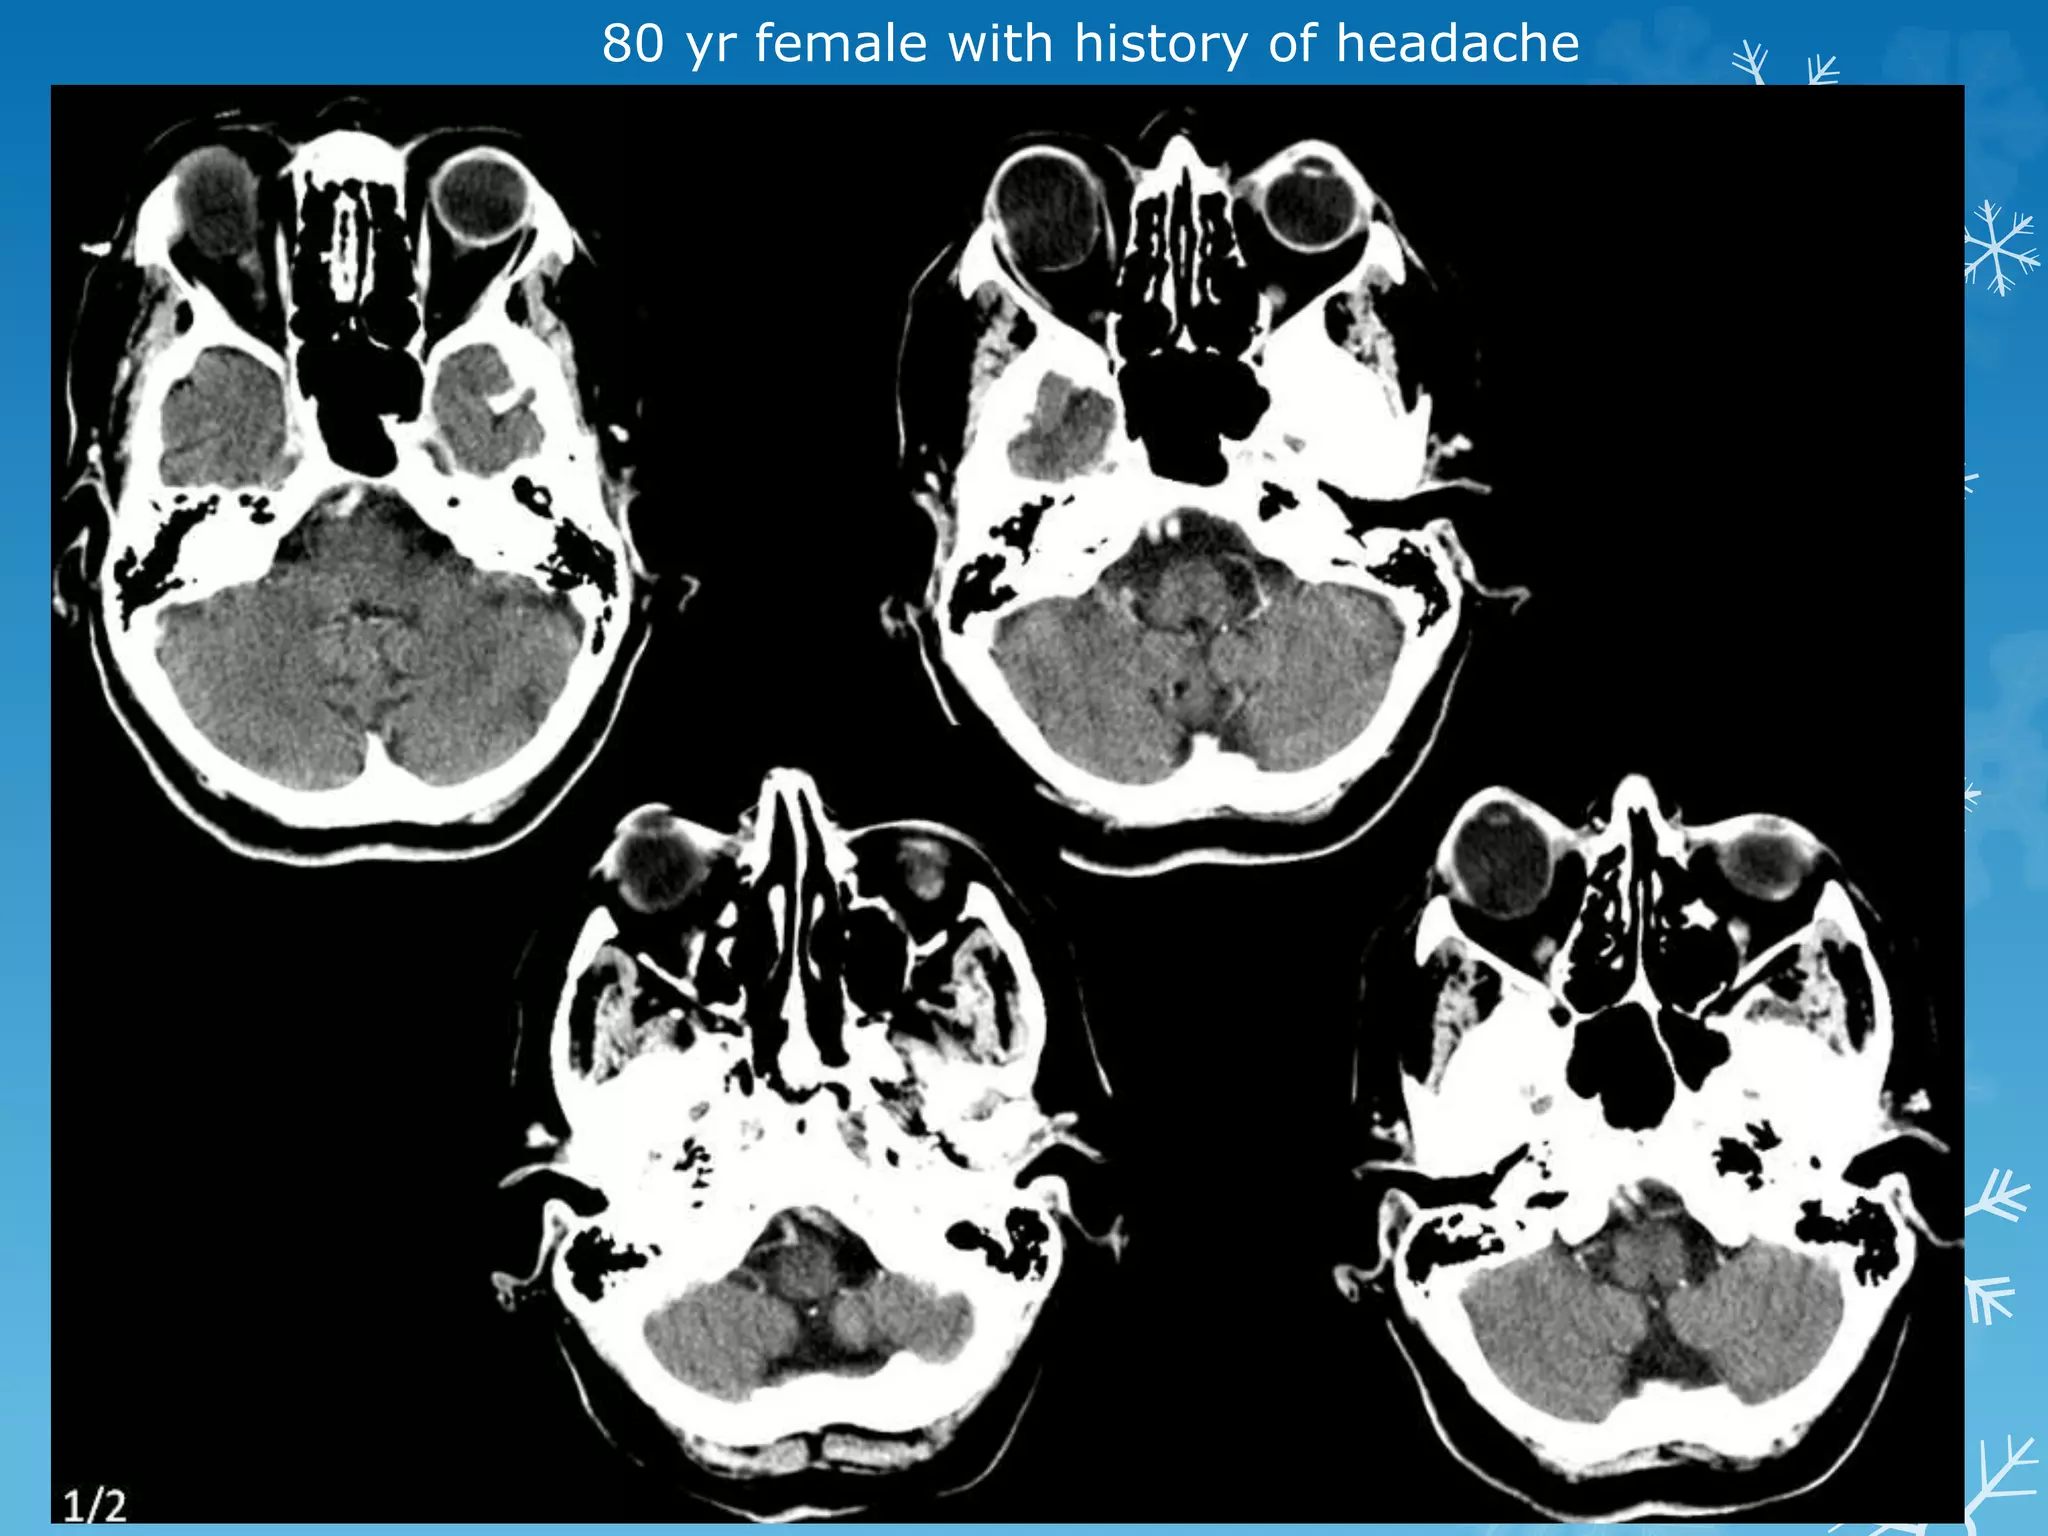

80 yr female with history of headache

80 yr femalewith history of headache